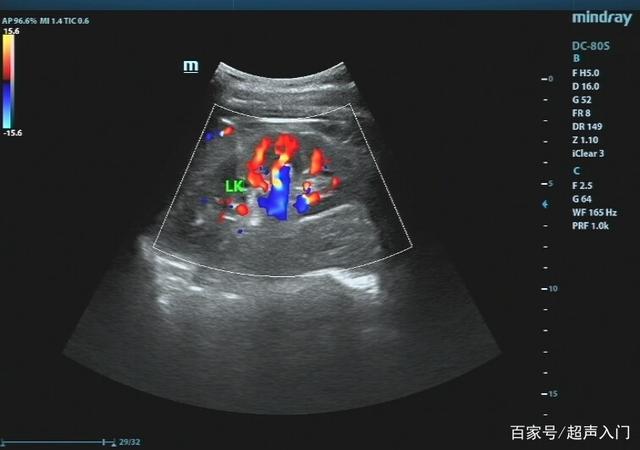

超声入门:肾结石超声诊断

长不大的肾肿瘤 - 超声医学讨论版 - 爱爱医医学论坛

一例后肾腺瘤超声表现病例分析

各类肾脏病超声图像表现